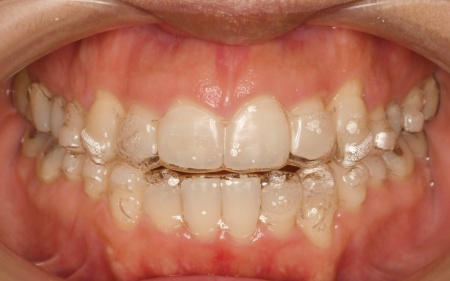

拝見したところ、奥歯で噛んだ際に上下の前歯が触れ合わず、隙間ができている状態でした。

これは開咬(かいこう)と呼ばれ、前歯で食べ物を噛み切るのが難しい噛み合わせです。

加えて全体的に歯が重なり合ってデコボコに生えており、歯磨きがしにくく、審美性にも悪影響がでています。

さらに舌で前歯を押す癖もあり、これは開咬の原因だけでなく、矯正治療後に歯並びが戻る原因にもなります。